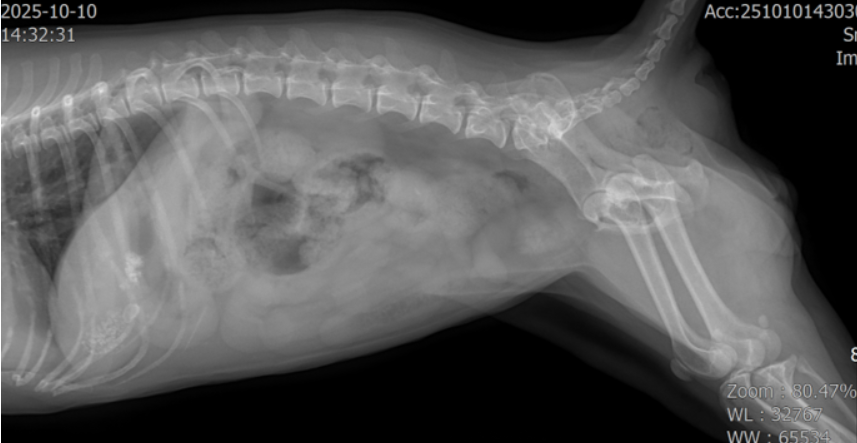

X-ray

방광(bladder) 부위에 다수의 방광결석(cystolith)이 의심되는 음영이 확인되었습니다.

초음파에서 bladder 내 다수의 방광결석,urethra 쪽으로 내려간 결석들,bladder wall 비후(방광염 소견)가 동시에 확인되었습니다.